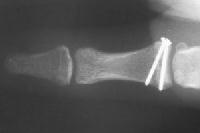

Injuries associated with a large avulsion fracture can be repaired with one or two micro screws, as was done here:

Click for larger image